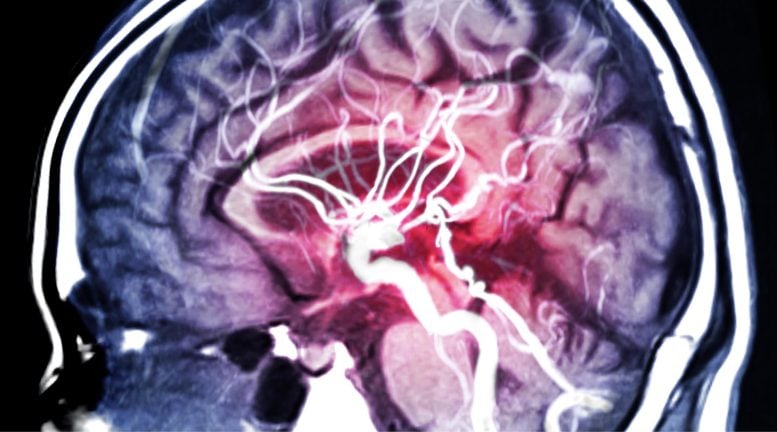

Tăng huyết áp âm thầm tàn phá não bộ trước khi chỉ số huyết áp tăng – Ảnh: Stock